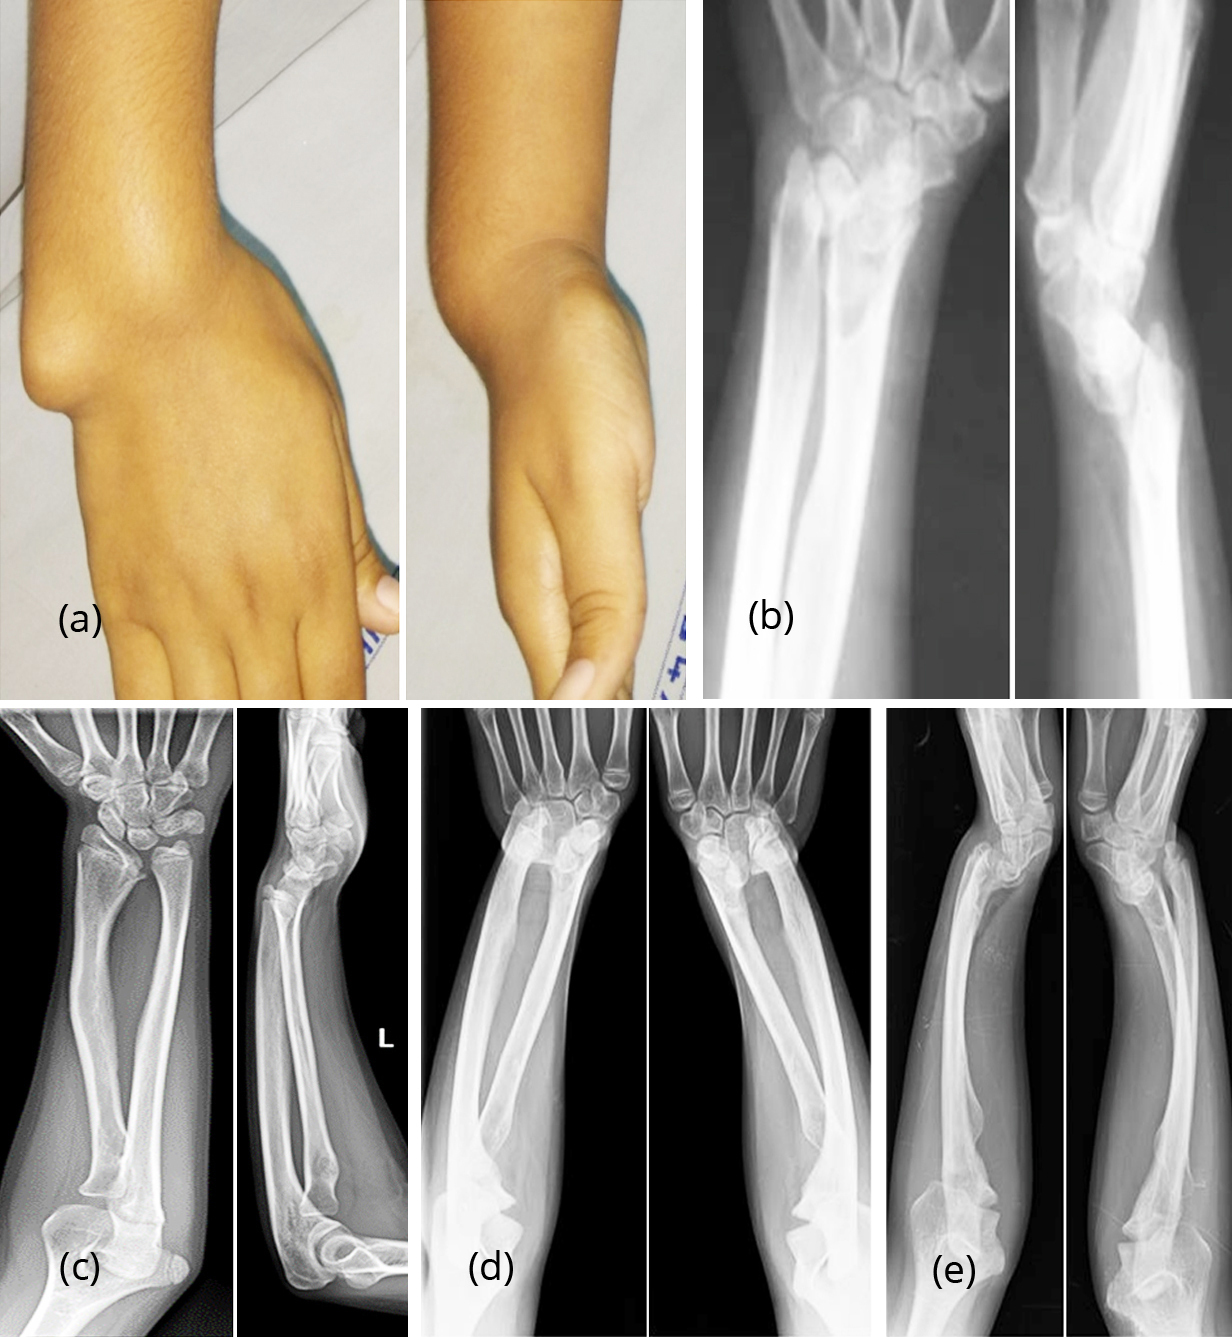

Madelung deformity. It comprises: (a) short distal radius, which shows a dorsal and ulnar curve;

(b) triangular shape of the distal radial epiphysis;

(c) premature fusion of the ulnar side of the distal

radial epiphysis;

(d) dorsal subluxation of the distal ulna;

(e) enlarged and distorted ulnar head; and

(f) wedging of the triangular-shaped carpus between the distal radius and ulna.

1. Isolated – bilateral > unilateral. Asymmetrical. Predominantly adolescent or young adult women.

2. Dyschondrosteosis (Leri–Weil disease) – bilateral with mesomelic limb shortening. AD. Predominantly men.

3. Diaphyseal aclasis.

4. Turner’s syndrome*.

5. Post-traumatic.

6. Postinfective.